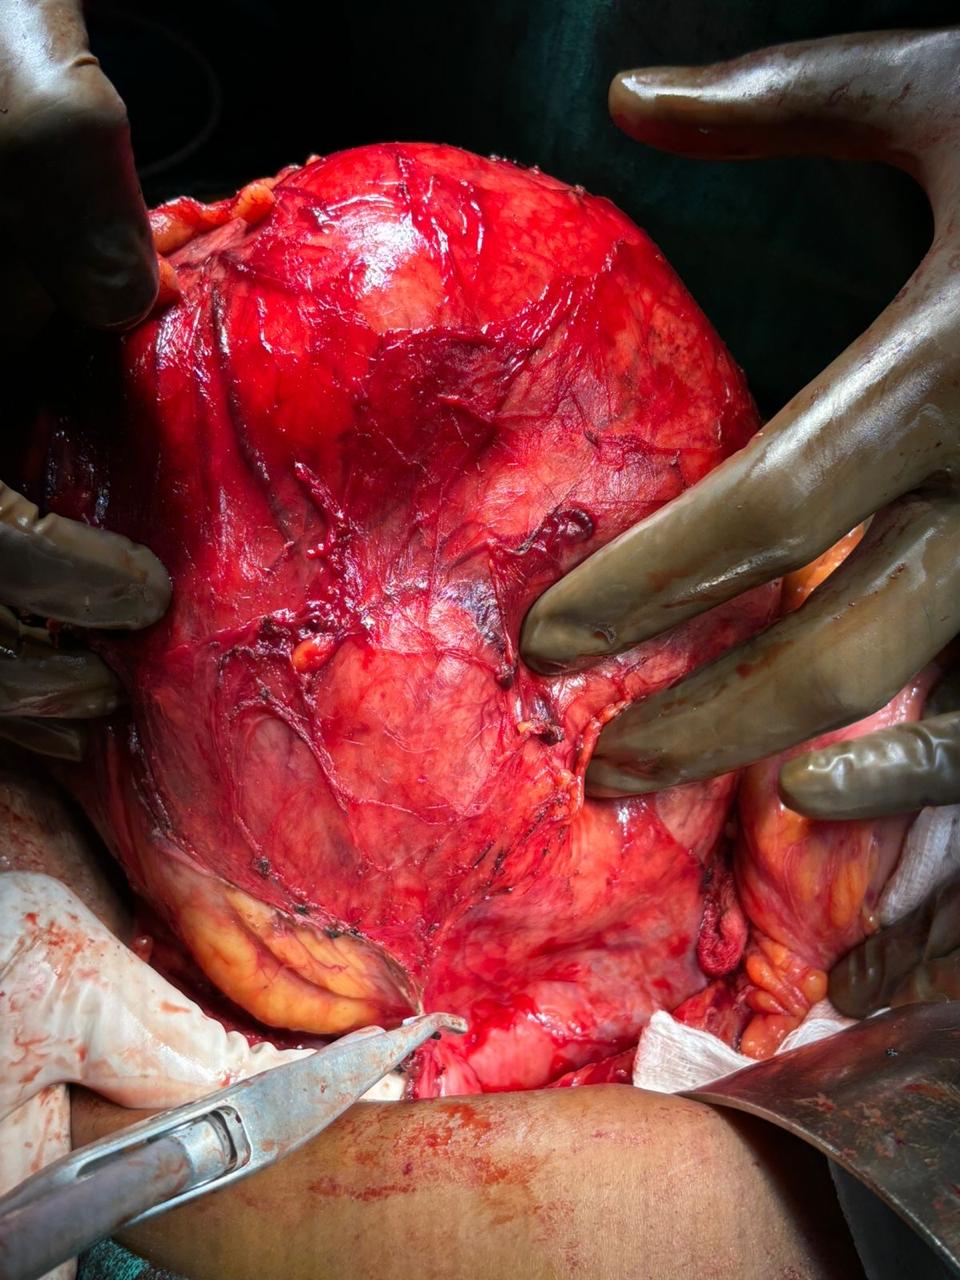

Our Gallery